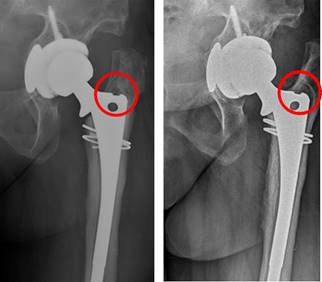

En relación con los parámetros radiológicos de aflojamiento, no se encontró que el número de zonas de Gruen afectas o que la suma en milímetros de las dimensiones de las zonas aflojadas mostrara diferencias estadísticamente significativas entre los dos grupos (p = 0.429 y p = 0.524 respectivamente). Sí se apreció una mayor afectación del área 7 de Gruen en el grupo control (78.9%) que en los casos (22.2%) (p = 0.01). Otras tendencias relevantes sin significación incluyen que el aflojamiento en zona 1 fue más frecuente en fracturas AG de Vancouver, el aflojamiento en zona 2 se produjo frecuentemente en fracturas tipo B2 (Figura 3).

Figura 3: Fractura periprotésica Vancouver B2. Nótese las imágenes sugerentes de aflojamiento en zonas de Gruen 2 y 6, así como la imagen compatible con desgaste del polietileno.